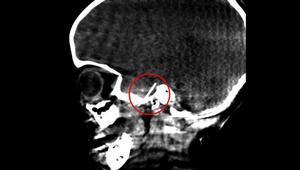

Anquiloglosia: una dolencia frecuente y leve cuya solución puede acabar en urgencias